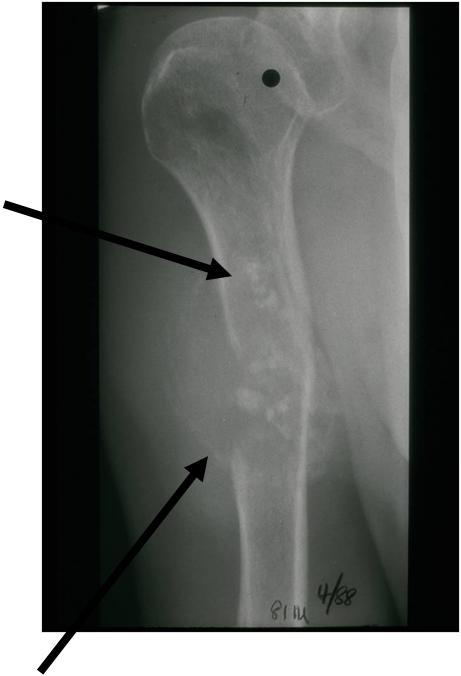

Radiographic Presentation

Radiology emulates pathology: Biphasic Tumor

- One region low grade chondrosarcoma

- Second more aggressive area with bone destruction, lysis of calcification, soft tissue mass

- Cortical permeation and a soft tissue mass in 70% of cases

Ill-defined, lytic intraosseous lesion

- Or extraosseous soft tissue mass

- Devoid of calcifications in continuity with lesions having the features of a cartilaginous tumor

Characteristically abrupt transition between chondroid tumor and dedifferentiated, lytic component

Bone may be expanded and adjacent cortex thickened

(Right Arrow)Aggressive Lytic Area (Dedifferentiated Sarcomatous Component) Cortical Destruction Soft Tissue Mass without Calcification